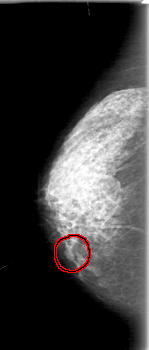

D_4079_1.RIGHT_MLO

RIGHT_MLO LINES 5131 PIXELS_PER_LINE 2521 BITS_PER_PIXEL 12 RESOLUTION 43.5 OVERLAY

FILE: D_4079_1.RIGHT_MLO.OVERLAY

TOTAL_ABNORMALITIES 1

ABNORMALITY 1

LESION_TYPE MASS SHAPE LOBULATED MARGINS OBSCURED

ASSESSMENT 0

SUBTLETY 3

PATHOLOGY BENIGN

TOTAL_OUTLINES 1

BOUNDARY